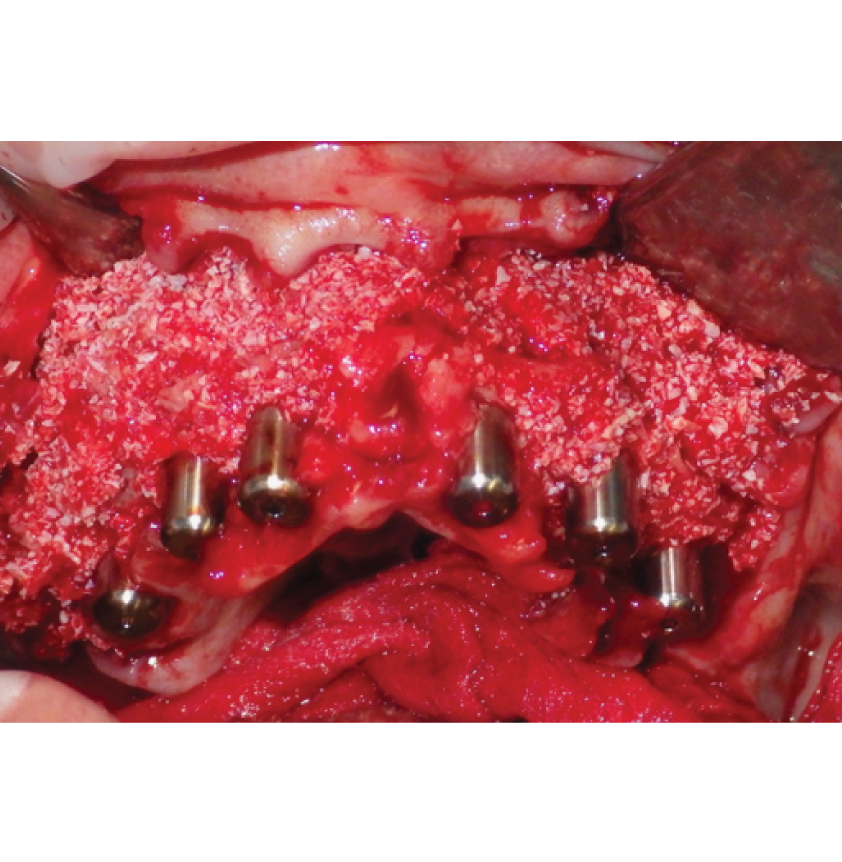

Director’s Clinical Cases

Director’s Clinical Cases